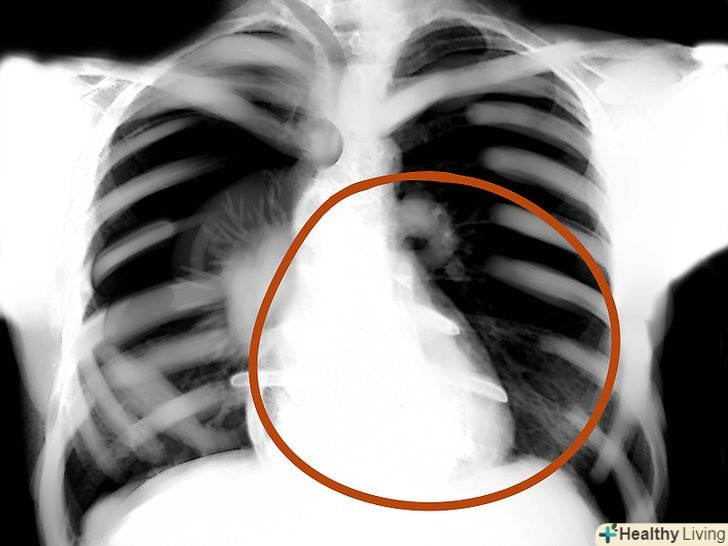

Дивлячись на знімок, потрібно пам'ятати, що це двомірне уявлення тривимірного об'єкта, де є висота і ширина, але немає глибини. Також потрібно пам'ятати, що ліва сторона знімка - це правий бік людини, а права сторона, відповідно, лівий. Повітря на флюорографії-чорний, жир-сірий, м'які тканини і вода - світлі відтінки сірого, кістки і метал - білі. Чим щільніше тканина, тим вона біліше на знімку. Відповідно, чим менш щільні ті чи інші тканини, тим вони темніше.

Контур серця.зверніть увагу на біле місце між легенями-серце. У нормі на серце повинно припадати менше половини ширини грудей.- Якщо серце на pa-знімках нагадує пляшку води-потрібна комп'ютерна томографія, щоб виключити наявність ексудату в області перикарда.

Межі серця, зовнішні м'які тканини.оцініть зникнення в нормі визначається контуру серця - так можна виявити пневмонію. Крім того, перевірте зовнішні м'які тканини на предмет патологій - збільшених лімфовузлів, підшкірних емфізем і т. д.

Області легенів.оцініть симетричність, васкулярність, наявність сторонніх мас, вузликів, інфільтрату, рідини і т.д. якщо в легкому слиз, кров, гній, пухлина або щось ще-то ця область буде яскравіше, а інтерстиціальні позначки - менш помітні.